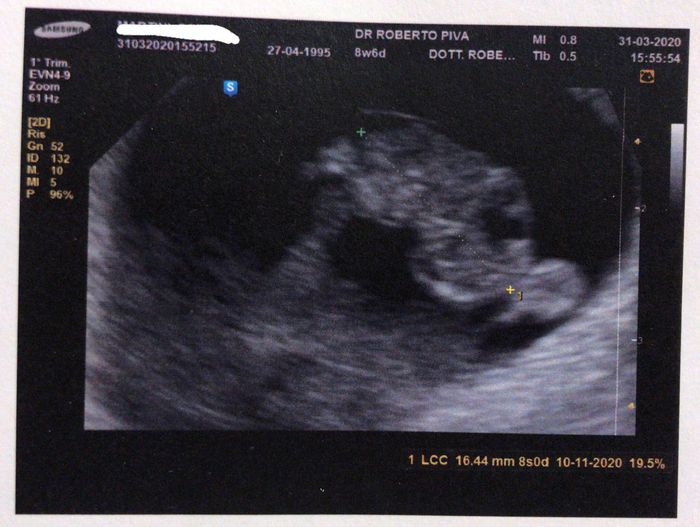

Non ti scoraggiare, queste sono le mie...5 settimane, 8settimane e 11 settimane, crescono dal giorno alla notte, a 8 era 1,6 cm e a 11 già 4,5 cm😍

Eco 5+5 1

Eco 5+5 2

Eco 5+5 3